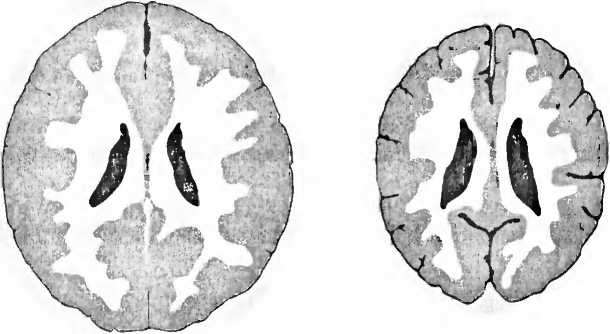

Человек появляется на свет с мозгом, который благодаря генетическому оснащению индивида и его внутриутробному развитию является абсолютно уникальным и в котором уже в значительной степени запечатлены его характер, таланты и ограничения (см. IV.1–4, IX, 1). Защищающее, стимулирующее окружение, которое ставит выполнимые требования перед ребенком после его появления на свет, стимулирует рост мозга. Еще в 1871 году Дарвин отметил, что мозг у зайцев и кроликов, выросших в тесной клетке, был на 15–30 % меньше, чем у росших на воле. И обратно: мозг был крупнее и было больше контактов между клетками мозга у тех животных, которые развивались в обогащающем окружении, просторной клетке со множеством вещей, которые каждый день обновляли, и где животные могли играть друг с другом. У детей, которым совершенно не уделяли внимания на ранней стадии развития, мозг также уменьшен (рис. 6): они на всю жизнь сохраняют ограничения, среди прочего — в интеллекте, языке и тонкой моторике, они импульсивны и гиперактивны. Прежде всего это сказывается на уменьшении префронтальной коры головного мозга. С другой стороны, сироты, усыновленные в возрасте до двух лет, впоследствии могут достигать IQ 100, тогда как усыновленные в возрасте от двух до шести лет, остаются на уровне IQ 80.

Рис. 6. Справа — томограмма мозга сильно запущенного трехлетнего ребенка, и для сравнения — томограмма мозга ребенка такого же возраста с нормальным развитием мозга (слева). У запущенного ребенка мозг значительно меньше, с увеличенными желудочками вентрикулами, полостями, черного цвета), по сравнению с мозгом нормально развивавшегося ребенка того же возраста. Кроме того между мозговыми извилинами видны увеличенные пространства из-за сморщивания (атрофии) коры больших полушарий (В. D. Perry, 2002).